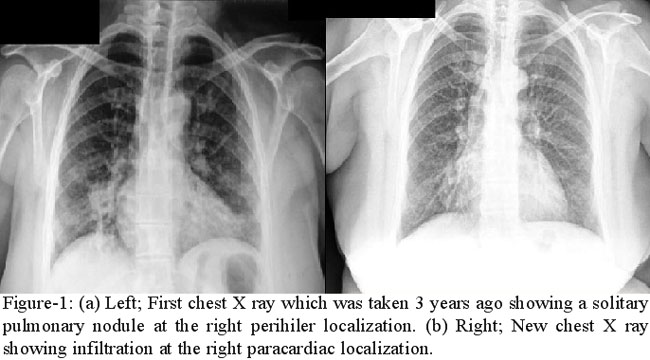

A 50 year old female patient was admitted with a 3 month history of haemoptysis. Physical examination, full blood count and biochemical analysis were normal. She had a 20 packet/year smoking history. In her medical record, she had a past history of pneumonia which was 3 years ago and at that time a 2.2 cm solitary pulmonary nodule located at the right perihilar location was detected in her chest X ray but patient did not accept any further intervention and remained asymptomatic upto date (Figure-1a).

Chest X ray showed infiltration at the right paracardiac localization (Figure-1b).Computerized tomography of the thorax revealed mediastinal lymphadenopathy with a diameter of 15 mm, consolidation located at the right middle lobe containing air bronchogram and with adjacent asiner nodules and ground glass opacification. Tumour, tuberculosis, pneumoni, hydatid disease were taken into differential diagnosis. Sputum acid fast bacteria evaluation taken three times were negative. Because there was a suspicion of tumour and because the patient did not accept intervention PET (positron emission tomography) was taken to exclude malignancy although it is not a first line of investigation in suspected malignancies. PET revealed low SUV max value (2.8) in the lymp nodes and right middle lobe consolidation area and this was interpreted as inflamation.